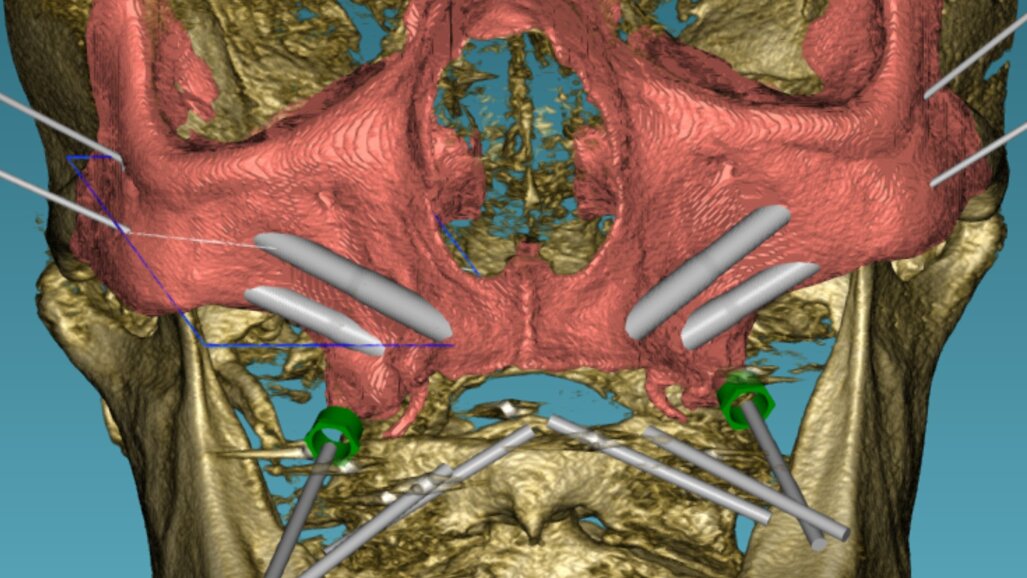

2. Diagnostiek en digitale behandelplanning

Gezien het extreem beperkte botvolume werd gekozen voor een vaste maxillaire rehabilitatie met een zygomatisch implantaatconcept, waarbij augmentatieve reconstructies werden vermeden. Met behulp van digitale planning in JDreal-software werden twee zygoma-implantaten en twee nasale/anterior-implantaten virtueel gepositioneerd (figuur 12). Op basis van deze planning werd een 3D metaal geprinte boormal ontworpen om een nauwkeurige, begeleide plaatsing volgens het geplande traject te kunnen garanderen.

Digitale planning van de implantaten (twee zygoma’s en twee nasale).

De chirurgie werd uitgevoerd onder lokale verdoving. Na een mid-crestale incisie werd een volledige flap opgeklapt met expositie van het zygoma. De 3D metaal geprinte boormal werd gefixeerd, waarna de implantaatkanalen werden voorbereid met een diamantboor. Vervolgens werden twee zygoma-implantaten (JD 3,9 × 37 mm) en twee nasale/anterior-implantaten (3,3 × 13 mm) geplaatst conform de digitale planning. Er werd een hoge primaire stabiliteit bereikt (>60 Ncm), waardoor directe belasting mogelijk was. In de onderkaak waren twee tissue level Straumann-implantaten geplaatst (figuur 13-15).